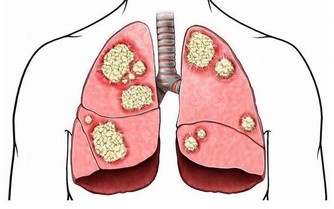

不管是何種酒,只要有酒精的酒,都會對肝臟造成不同程度的損傷。這是因為酒精被喝到肚子里之後,只有10%是在胃裡消化,其他的90%都是要通過肝臟代謝的。而酒精的主要成分乙醇會直接刺激、損傷肝細胞,所以您看成天喝酒的人,沒有一個肝是完全健康的。